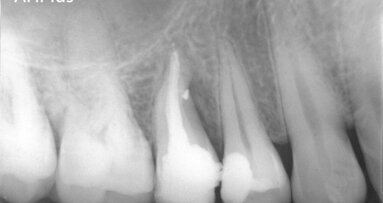

In a Europe-wide study conducted with about 600 dental professionals, the majority of testers of GuttaFlow bioseal ceramic from COLTENE were very satisfied or satisfied with the overall result of treatment. (Image: COLTENE)

Over the past few months, nearly 600 dentists from across Europe took part in a large-scale practice experiment in which special attention was paid to the handling of endodontic revision treatment. The specifically developed Remover revision files manufactured by COLTENE were used in combination with the GuttaFlow bioseal ceramic sealer.

During subsequent filling and sealing of the root canal with the GuttaFlow bioseal ceramic sealer, the rating of the properties respondents liked the most differed. Among other things, the obturation material supports regeneration by raising the pH level in the root canal. Hydroxyapatite crystals are formed on contact with bodily fluid. These are natural components of bone and tooth tissue and thus support the healing process. The majority of respondents (60%) named ease of handling as the most outstanding feature of the obturation material. Rapid polymerisation in only 12–16 minutes, good radiopaque visibility and flowability were also rated positively. Over 72% of the testers were very satisfied or satisfied with the overall result of treatment, and 75% of the dentists said that they could imagine continuing to use GuttaFlow bioseal in their practice in the future.